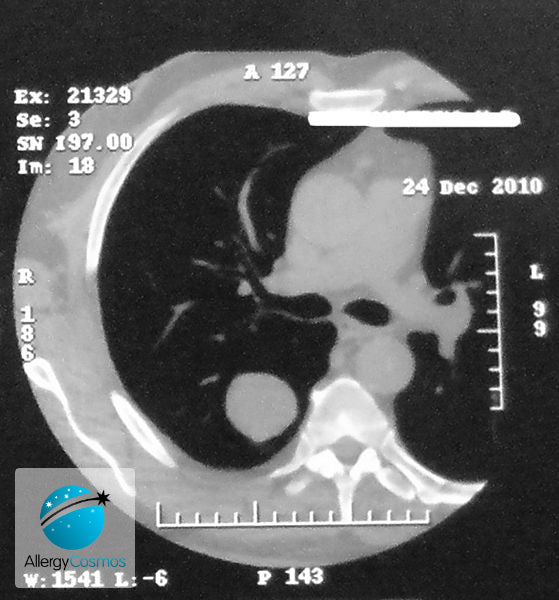

Cancer in solid organs like the liver, colon and lung arises from abnormal cells which clump together to form a tumour. When a tumour is in the lungs, it may be a primary tumour or a secondary tumour that has arisen from the spread of another primary cancer. This article talks about primary lung cancer and its causes. There are two types of lung cancer: small cell lung cancer and non-small cell lung cancer. The latter can be further sub-divided into various types including squamous cell and adenocarcinoma. These definitions are based on how the lung cancer cells look under the microscope.